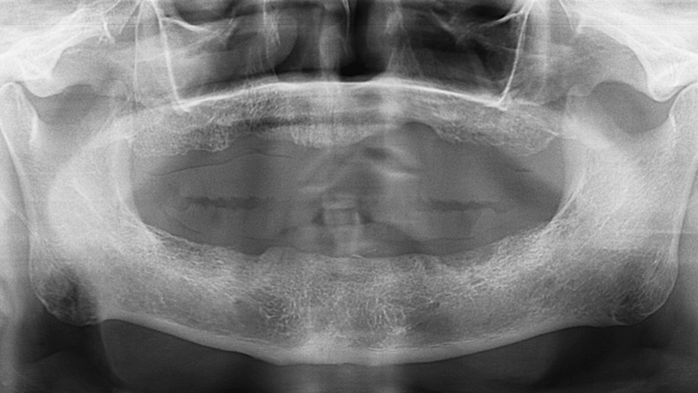

Clinical case: Preview the final goal first, make the ideal treatment plan, then realize it using the appropriate tools

- Courtesy of Dr. Sang Tack Lee, Korea -

Dr. Sang Tack Lee, edentulous, digital full mouth prosthetics, digital guided surgery, #11, #13, #14, #16, #17, #21, #23, #24, #26, #27, #33, #34, #36, #37, #43, #44, #46, #47, guided surgery, flapless, AnyRidge, R2GATE, Mega ISQ, MEG Torq, MEG Engine, R2GATE Full surgical kit